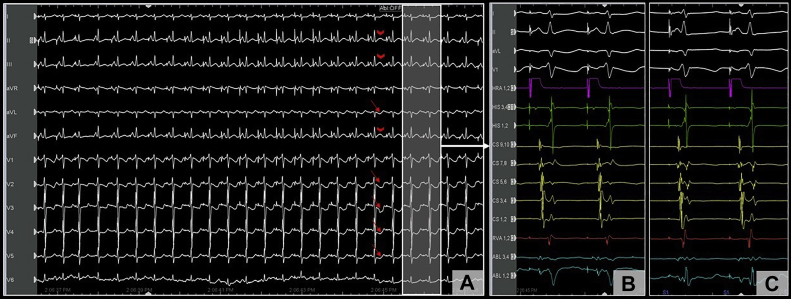

Following this, isoproterenol (10 mcg intravenous bolus) was administered, and testing was repeated with abolition of AH jump. Approximately 4 minutes after isoproterenol administration, the patient developed spontaneous VF from an R-on-T premature ventricular contraction (Figure 1B), requiring defibrillation. This rather unusual finding raised suspicion for CA injury, and review of the surface 12-lead electrocardiogram (EGC) at a 25 mm/s sweep speed showed precordial ST-segment depression (Figure 2A, red arrows) with subtle elevation in the inferior leads (Figure 2A, red arrowheads) after 1 of the ablation lesions (Figure 1A, red arrows). The 12-lead ECG during the entire ablation lesion as well as a plot of biophysical parameters during this ablation lesion are shown in Supplemental Figure S1; there was a gradual increase in impedance of >10 Ω, after which ablation was terminated. These subtle ECG changes post ablation were not evident on 200 mm/s sweep speed that is used during EP study and ablation (Figure 2B and C). Emergent coronary angiography was performed with a JR4 guide catheter, which revealed complete occlusion of the right posterolateral branch of the right CA (Figure 3A and D). Intracoronary nitroglycerin and verapamil were administered through the guide catheter, without improvement in appearance or flow. Percutaneous transluminal coronary angioplasty (PTCA) was performed, which resulted in flow restoration. However, there was residual stenosis followed by complete reocclusion resulting in ST changes and another episode of VF requiring defibrillation. Repeat PTCA was attempted, with administration of additional vasodilators; however, the vessel continued to occlude, suggesting extrinsic compression from myocardial edema or direct thermal injury to the artery. Coronary stenting was performed with a Xience Alpine 2.25/15 drug eluting stent (Abbott Laboratories), with successful resolution of ST changes and TIMI 3 flow with good myocardial blush (Figure 3B and E).

Figure 2.

A: Electrocardiogram at low sweep speed (25 mm/s) showing worsening ST changes during ablation, including ST depression (red arrows) in the precordial leads and subtle ST elevation (red arrowheads) in the inferior leads. These changes (highlighted area with white arrow) were less apparent on the higher sweep speed with limited precordial leads (B) when compared to the ST segment prior to ablation (C).